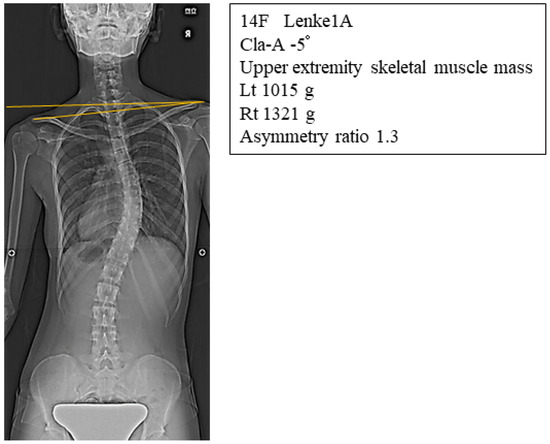

| Cla-A (°) | −1.4 ± 2.8 | 0.48 ± 1.8 | p < 0.05 |

| RSH (mm) | −10.5 ± 13.1 | 0.93 ± 10.9 | p < 0.05 |

| Cla-A (°) | R | −0.56 | −0.54 |

| p | <0.05 * | <0.05 * | |

| RSH (mm) | R | −0.52 | −0.52 |